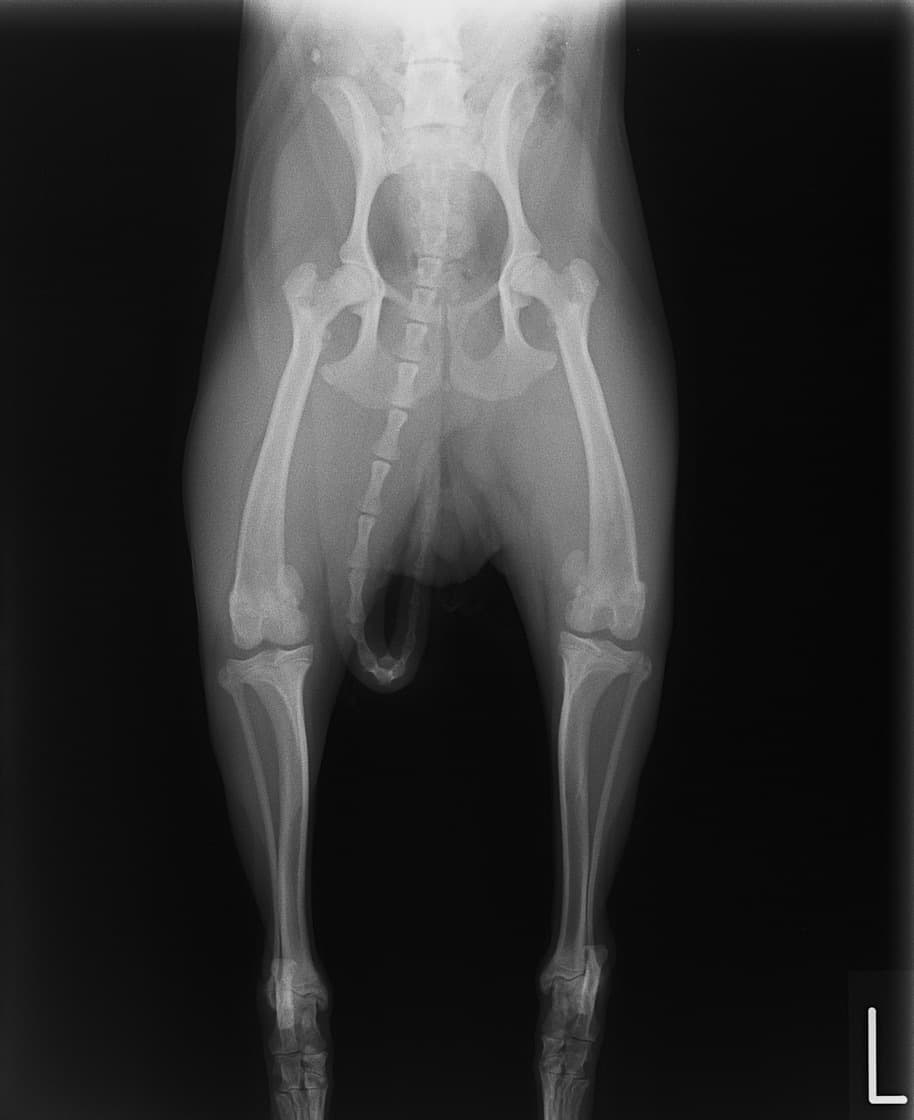

■ 症例24 キャバリア 7か月

左右膝蓋骨内方脱臼(左:グレードⅣ 右:グレードⅢ)

以前から左右後肢の跛行が認められ、整形外科学的検査・レントゲン検査により左右の膝蓋骨脱臼が認められた。症状が重度である左膝の膝蓋骨脱臼整復術を行った。外科手技は縫工筋及び内側広筋の解放、脛骨粗面の外側転位、滑車ブロック形造溝術、内外側関節方の縫縮を実施した。術後一か月時点で、左の膝蓋骨は安定しており経過は良好である。

本症例は成長期における重度の膝蓋骨脱臼であり、術後の再発の可能性もあるため、経過をしっかりと観察していく必要がある。また、今回手術を実施していない右膝に関しても経過を観察し、手術を検討していくこととする。